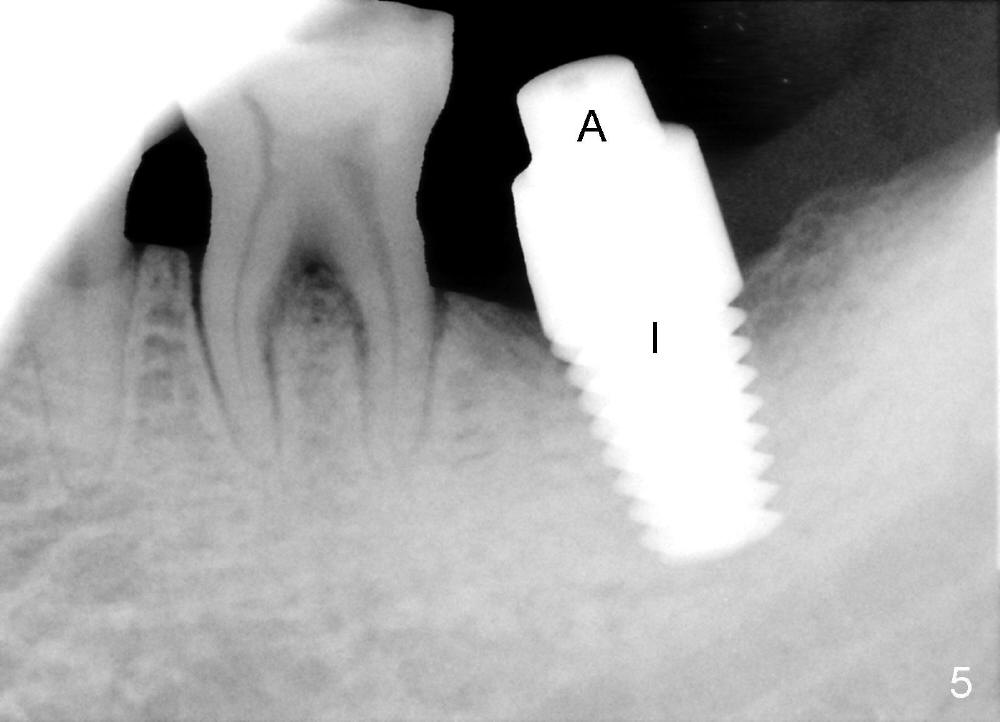

The soft tissue heals around the implant 1 months postop (Fig.1), but the implant (7x11 mm) is unstable. It should have been placed 2 mm deeper (Fig.2).  It is splinted for the neighboring tooth (Fig.3).  When the splint is removed 4 months later, the implant remains mobile.  It is removed with infiltration anesthesia.  The osteotomy is deepened by approximately 2 mm.  A 7x14 mm tap is inserted with stability (Fig.4); there is apical space to be engaged further (arrowheads).  A 7x14 mm implant is placed with insertion torque > 60 Ncm (Fig.5 I); an abutment (A) placed to keep perio dressing in place.